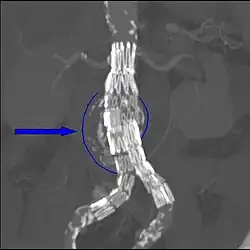

- EndoAnchors: Small, helically shaped devices are screwed through the endograft and into the aortic wall. EndoAnchors have been used successfully to treat endoleaks and, in concert with an aortic extension endograft, to treat migration of the original endograft.[26] Rigorous evaluations and long-term outcomes of this technique are not yet available.